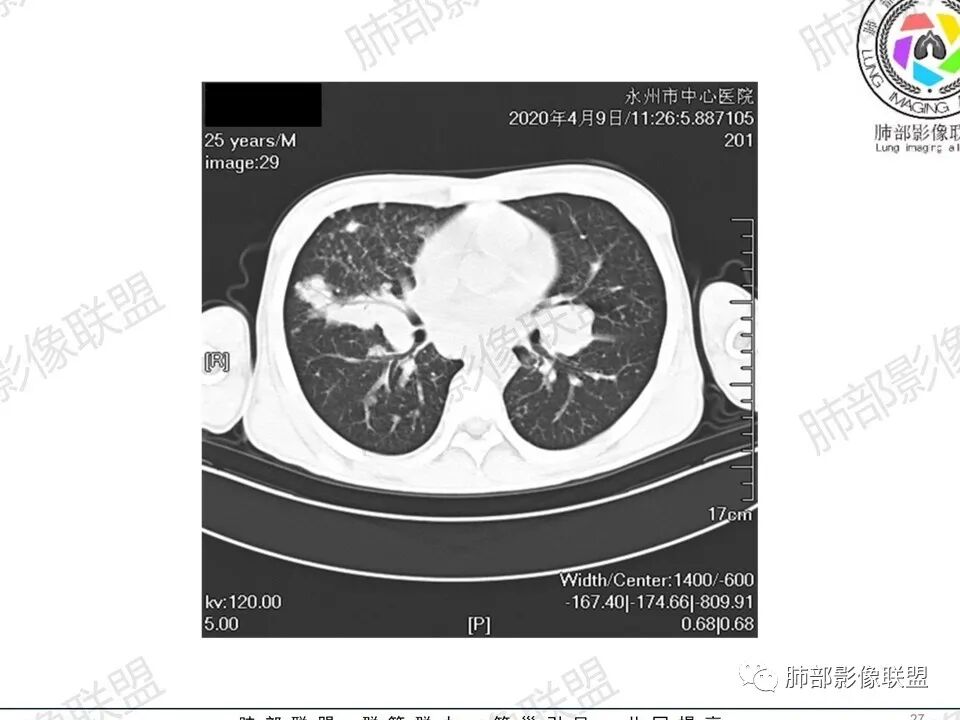

那个人:青年男性,慢性病程,咳嗽气促,伴盗汗胸痛。实验室,贫血,血沉快,C反应蛋白升高,低蛋白血症。影像,双肺散在斑片影,结节影,伴树芽,斑片影源支气管血管束分布,支气管走形自然,结节影有小空洞,有些周围有磨玻璃成分,小结节有些成串珠样改变,纵隔肺门淋巴结肿大,心腔低密度。考虑淋巴增值类疾病,结核?淋巴瘤?结节病?鉴别血管炎,实验室,影像不太支持

一切∮随缘:双肺多发大小不等结节,结节密度高,边缘清楚,部分结节内可见血管穿行,另右肺长条状实变影,内部可见支气管充气征,局部支气管壁增厚,双肺多发小树丫,双肺门及纵隔淋巴结肿大,部分融合,无增强,对淋巴结坏死无法判断,临床:年轻男性慢性病史急性加重,血象、CRP、ESR高,考虑一元论:结核(年龄加影像都符合),二元论:结节病或淋巴瘤+结核(建议CT增强及淋巴结穿刺),无原发肿瘤病史,癌性淋巴管炎代排。

男性,25岁,咳嗽咳痰1年,气促两月,加重一天,伴盗汗胸痛。CT示双肺散在斑片影,结节影,树芽征,部分周围伴磨玻璃影,以右肺上叶明显,纵隔及双肺门可见多发淋巴结肿大,部分融合,青年人,病史较长,首先考虑结核,不排除结核合并结节病可能。

3、影像表现:双肺散在斑片影及结节影,部分结节内可见血管穿行,斑片影沿支气管血管束分布,近胸膜侧病变收缩不明显。部分中央淋巴间质增厚,小叶间隔增厚。病灶内支气管穿行,部分支气管略扩张。局部小结节呈串珠样改变。纵隔、肺门区、锁骨上及腋窝淋淋巴结肿大,部分有融合。心腔低密度。脾大。

2.双肺多发片影及结节影,边界可分辨,右肺中上叶较为密集,没有胸膜下分布优势。病灶实性密度为主,未见钙化及液化。

3.右肺较多微小结节,密度较为浅淡,部分沿血管束分布,未见沿小叶间隔及叶间裂分布结节影,未见典型的终末气道树芽。

4.病灶区域穿行支气管显示良好,未见壁增厚及管腔狭窄。

5.双肺门及纵隔淋巴结显著增大,这改变相当显眼。这里强调“双肺门”及“多发”!

增大的淋巴结密度偏低且均匀。此外患者有体表淋巴结增大。